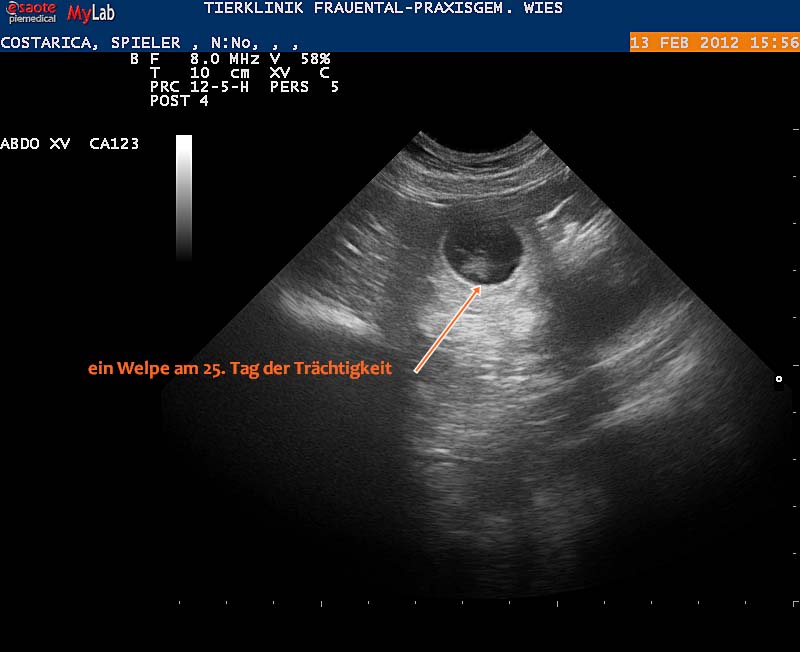

13.02.2012: Ultraschalltermin

Das Date der beiden am 20.1. hat Folgen. Der Tierarzt hat uns die Trächtigkeit von Costa-Rica bestätigt und wir freuen uns schon sehr auf den Nachwuchs.

Links: Eine Fruchtblase am 25. Trächtigkeitstag - Rechts: Ein Welpe 10 Tage später